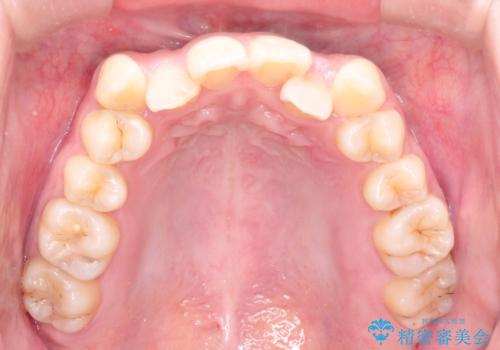

- 八重歯と前歯のガタガタを主訴に来院されました。

左下の奥歯がすでに1本抜歯されており、ブリッジを装着されていました。

ブリッジを除去して、左下以外の上顎両側と右下の歯を合計3本抜歯して矯正する計画としました。

ブリッジを装着している歯は動かすことができないので、矯正前に除去する必要があることがあります。

今回の場合も、ブリッジを除去して矯正後にセラミックブリッジを装着しました。